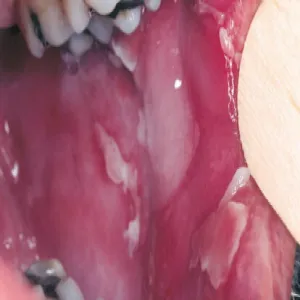

Pęcherzyca zwykła pospolita

Pęcherzyca zwykła

Grzybica jamy ustnej

Grzybica w jamie ustnej